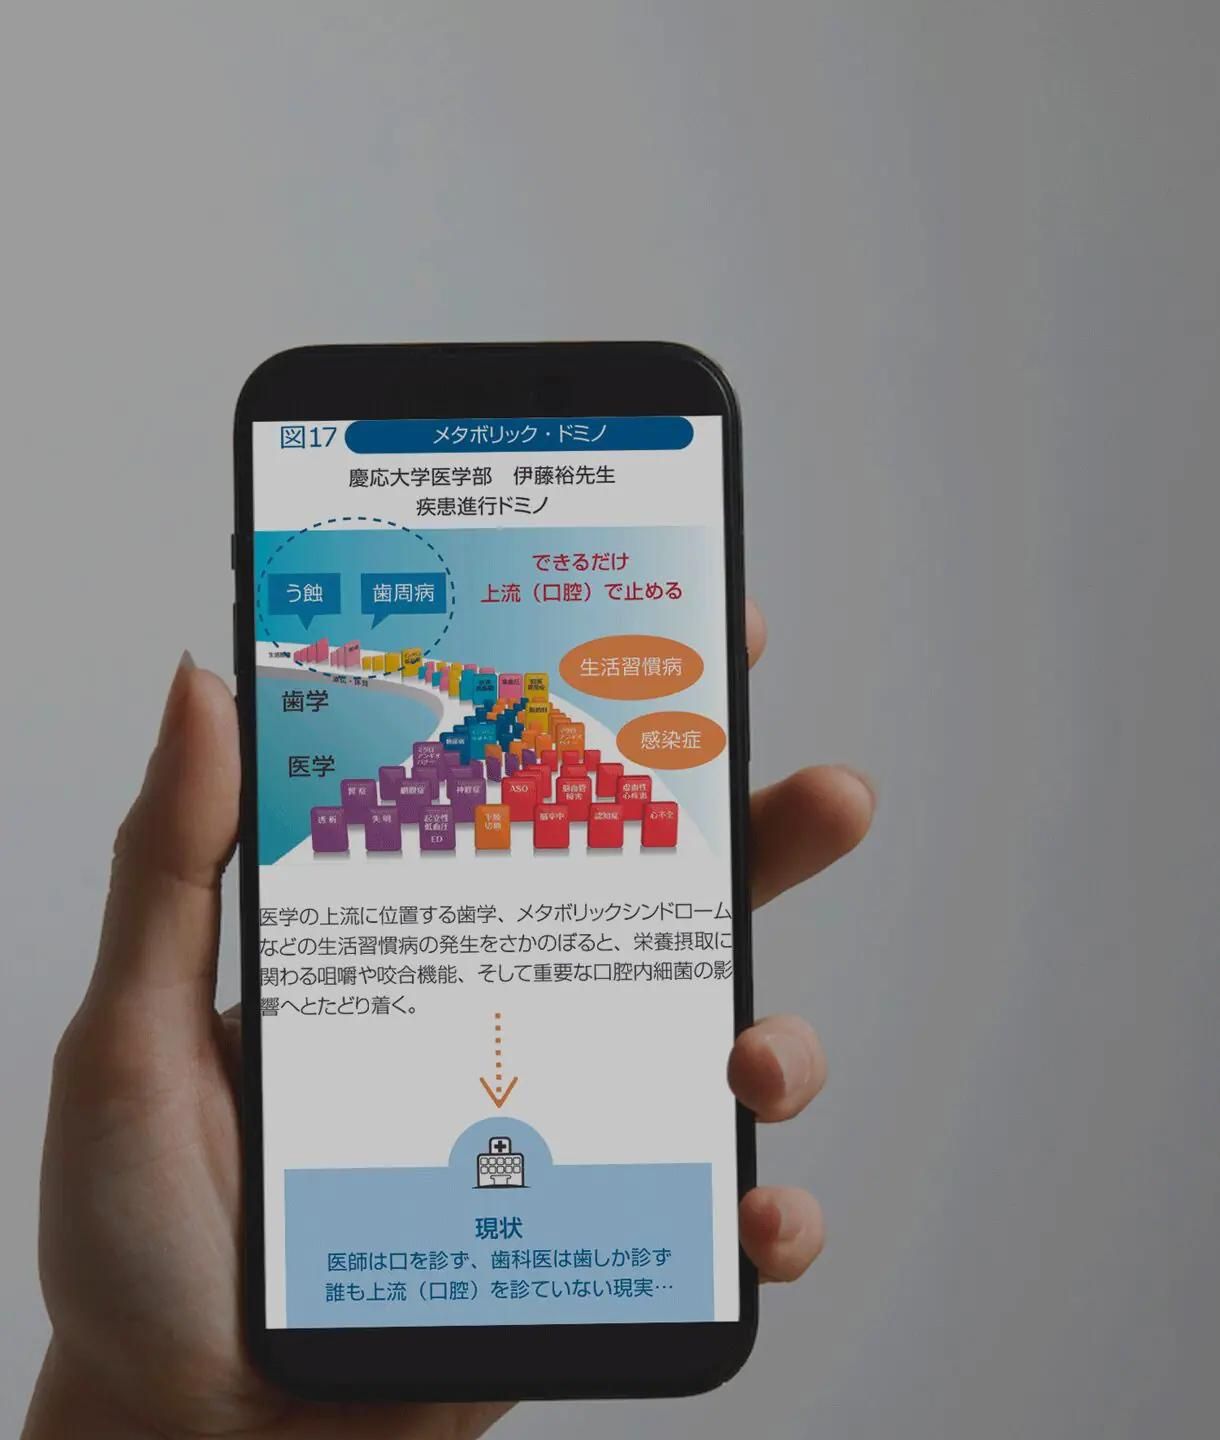

身体の健康はお口から

歯周病の予防・治療を行うことで、全身の様々な病気のリスクを下げることが可能です。日々の歯磨き・口腔ケアを見直し全身の健康につなげましょう。これらを予防・管理することは、メタボリック症候群や心臓病、糖尿病などの深刻な疾患のリスクを減少させます。口腔内の健康状態は全身の健康状態を反映し、適切な口腔ケアは全体的な健康管理と疾患予防の重要な一環です。早期の対策と定期的なケアで、より健康な生活を実現できます。